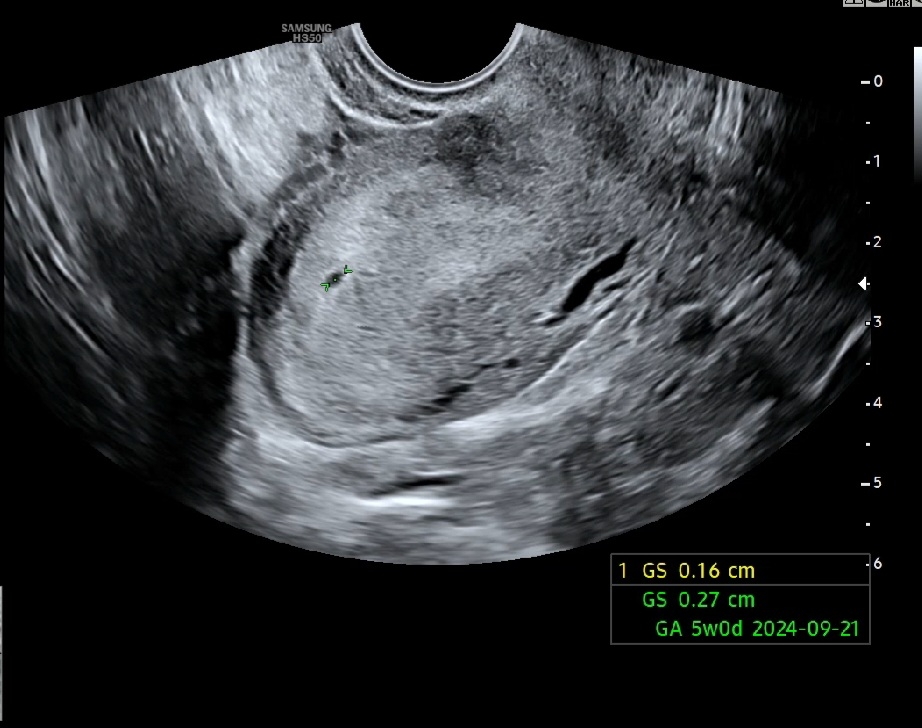

임테기 진하게 2줄이라 산부인과 간건데 (네이버 계산상 5주차!) 근데 의사쌤이 2줄 본거 맞냐고 애기집이 안보인다 해서 너무 맘쫄렸어요 ㅠㅠㅠㅠㅠ 결국 찾았어요! 너무 작아서 극초기래요 ㅎㅎㅎ5주가 아닌가봐요 0.16 cm ㅎㅎㅎ

너무 축하드려요~월요일날 첫 진료가는데 저도 아기집 보고 오고싶어요~~그리고 생리주기가 28일보다 긴편이시면 네이버 주수 안맞을수도 있으세요~ 네이버 기준이 28로 계산 하는거같더라구요? 잘모르지만ㅎㅎ 저도 네이버 주수로는 5주 나오는데 다른 사이트네 제 생리주기 33일 입력해서 하면 4주2일 떠요!!